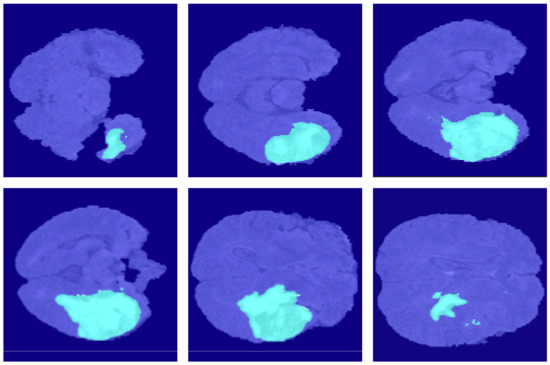

4.2. Segmentation Results

5.1. Ablation Experiment of Generative Mask Sub-Network